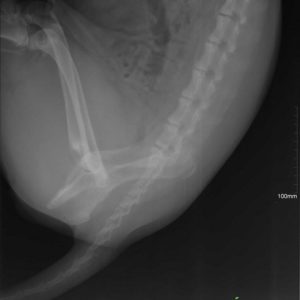

Zora túl van a műtéten és 5 nap után újra velünk van a menhelyen! A kedve jó, nincsenek fájdalmai és reméljük a 2 hónap pihenő után végre felszabadultan játszhat majd a többiekkel!